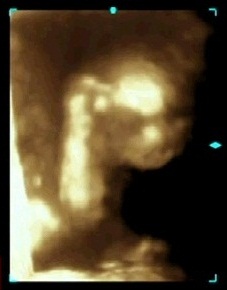

写真:21w2d:にきゆずさん

お顔を見せてくれました! お父さんとお母さんに似てお鼻が立派です! 429g!

正面向きで顔に沿わせた右手が見えます。

頭を掻いているのかな?